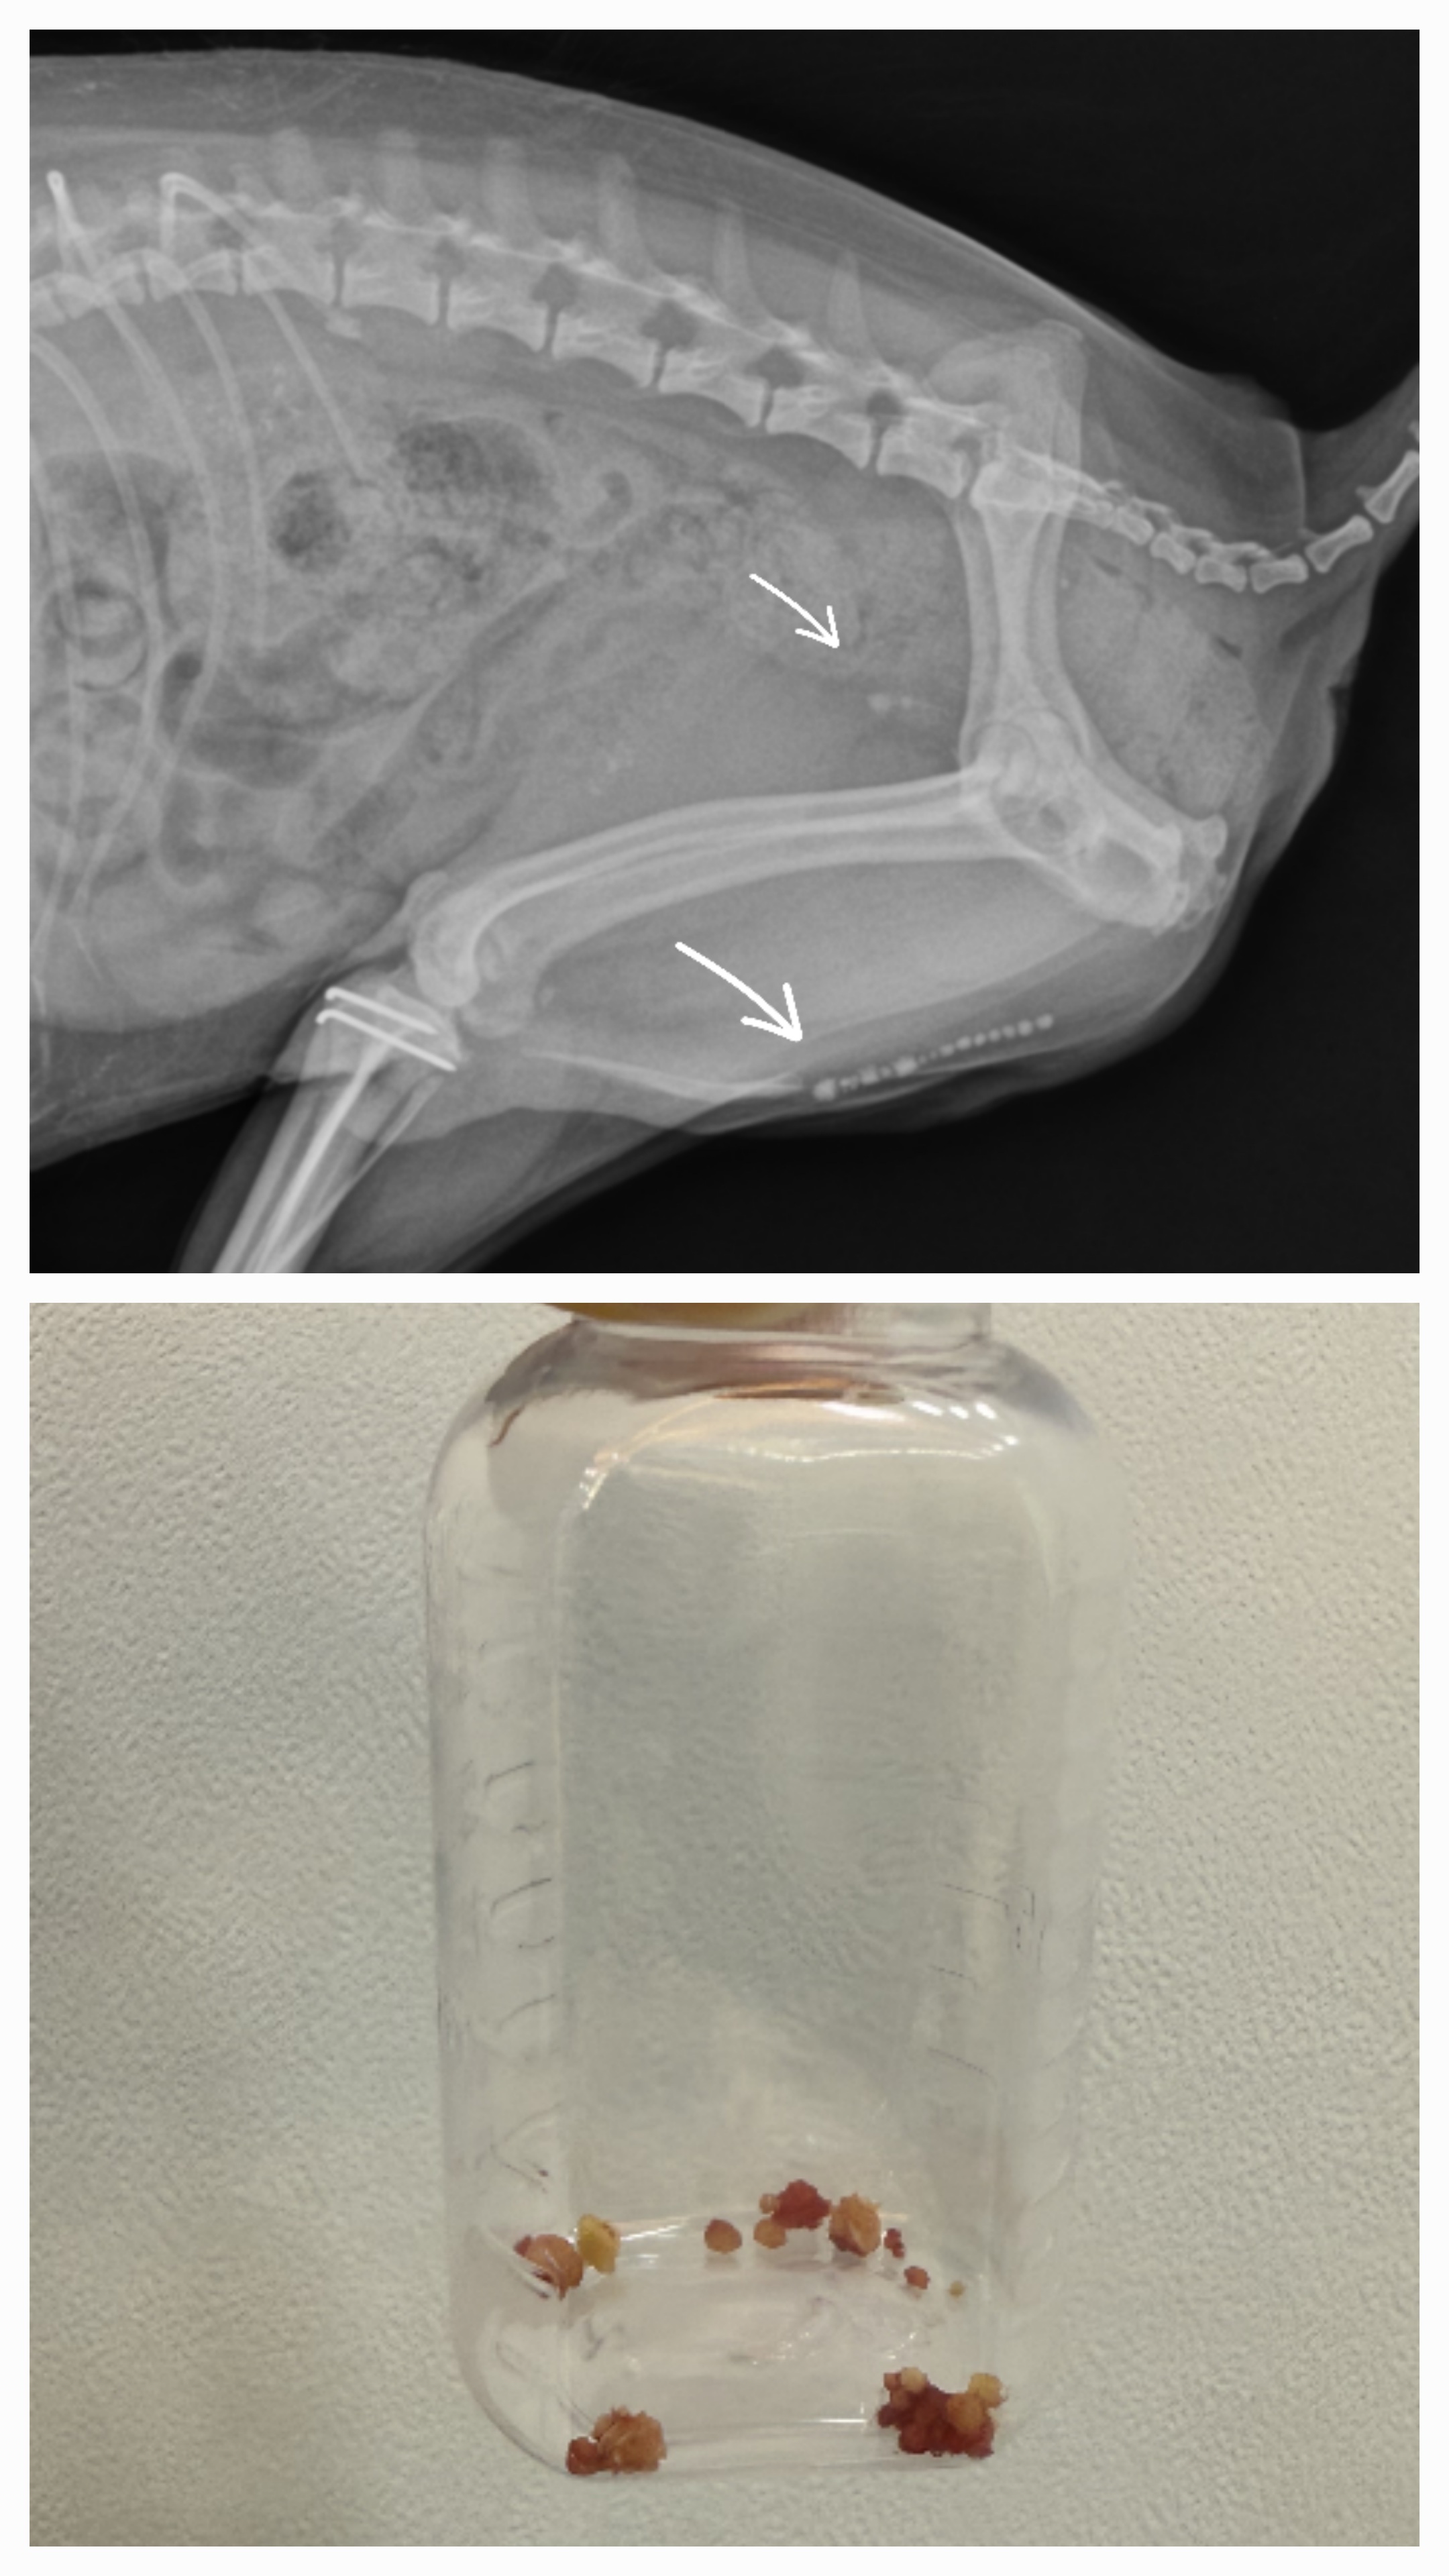

왕복 2시간 걸려 찾아온 강아지 방광결석 수술과정

7살 강아지 요도결석 수술사례

강아지가 피오줌이 나와요 - 방광결석